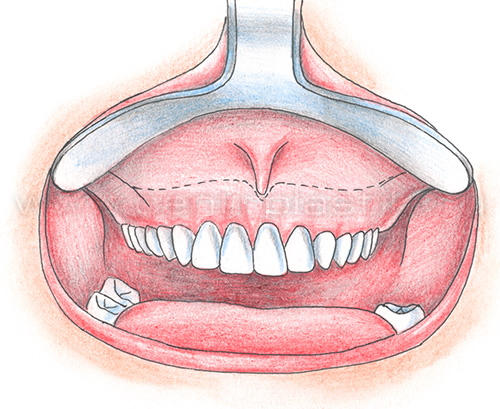

Остеотомия верхней челюстиПоказания Коррекция аномалий развития верхней челюсти (микрогнатия, ретрогнатия верхней челюсти). Остеотомию на верхней челюсти проводят как этап ортодонтического лечения. Операция Остеотомия верхней челюсти выполняется внутриротовым доступом под эндотрахеальным наркозом, выполняется разрез слизистой оболочки полости рта и надкостницы, разрез производят несколько выше переходной складки верхней челюсти от 7 до 7 зубов. Края раны раздвигаются, тем самым осуществляется доступ к передней стенке верхней челюсти.  На передних и боковых стенках верхней челюсти слева и справа производятся разметки линий распилов.  Специальными пилками проводится остеотомия по разметкам.  Затем отделяется распиленный фрагмент и перемещается в заранее выбранное положение.   Фиксация перемещенного фрагмента в новом положении осуществляется титановыми мини-пластинками.  Длительность Операция занимает от 1,5 до 3 часов и проводится под наркозом. В течение 1 месяца после лечения сохраняется отечность мягких тканей лица, может отмечаться нарушение чувствительности верхней губы и щек, чувствительность восстанавливается самопроизвольно через некоторое время. В ряде случаев после операции для обеспечения хорошего срастания костей проводят межчелюстное шинирование , верхняя и нижняя челюсти фиксируются друг к другу специальными приспособлениями, так что полное открытие рта невозможно. В этот период (2-3 недели) возможно питание только протертой и жидкой пищей. После операции остеотомии верхней челюстиВ послеоперационном периоде возможно ношение ортодонтической брекет системы для правильного смыкания зубных рядов верхней и нижней челюстей. Реабилитационный период В течение 1-3 суток после операции рекомендовано нахождение в стационаре под наблюдением медицинского персонала (длительность нахождения в стационаре может быть продлена до 10 суток в зависимости от течения послеоперационного периода). Длительность реабилитационного периода зависит от восстановительных способностей организма. Эффективность Окончательный результат операции можно наблюдать через 3-6 месяцев. В послеоперационном периоде могут сохраняться отеки в течение 2-4 недель, в зависимости от индивидуальных особенностей восстановление протекает с разной скоростью. |